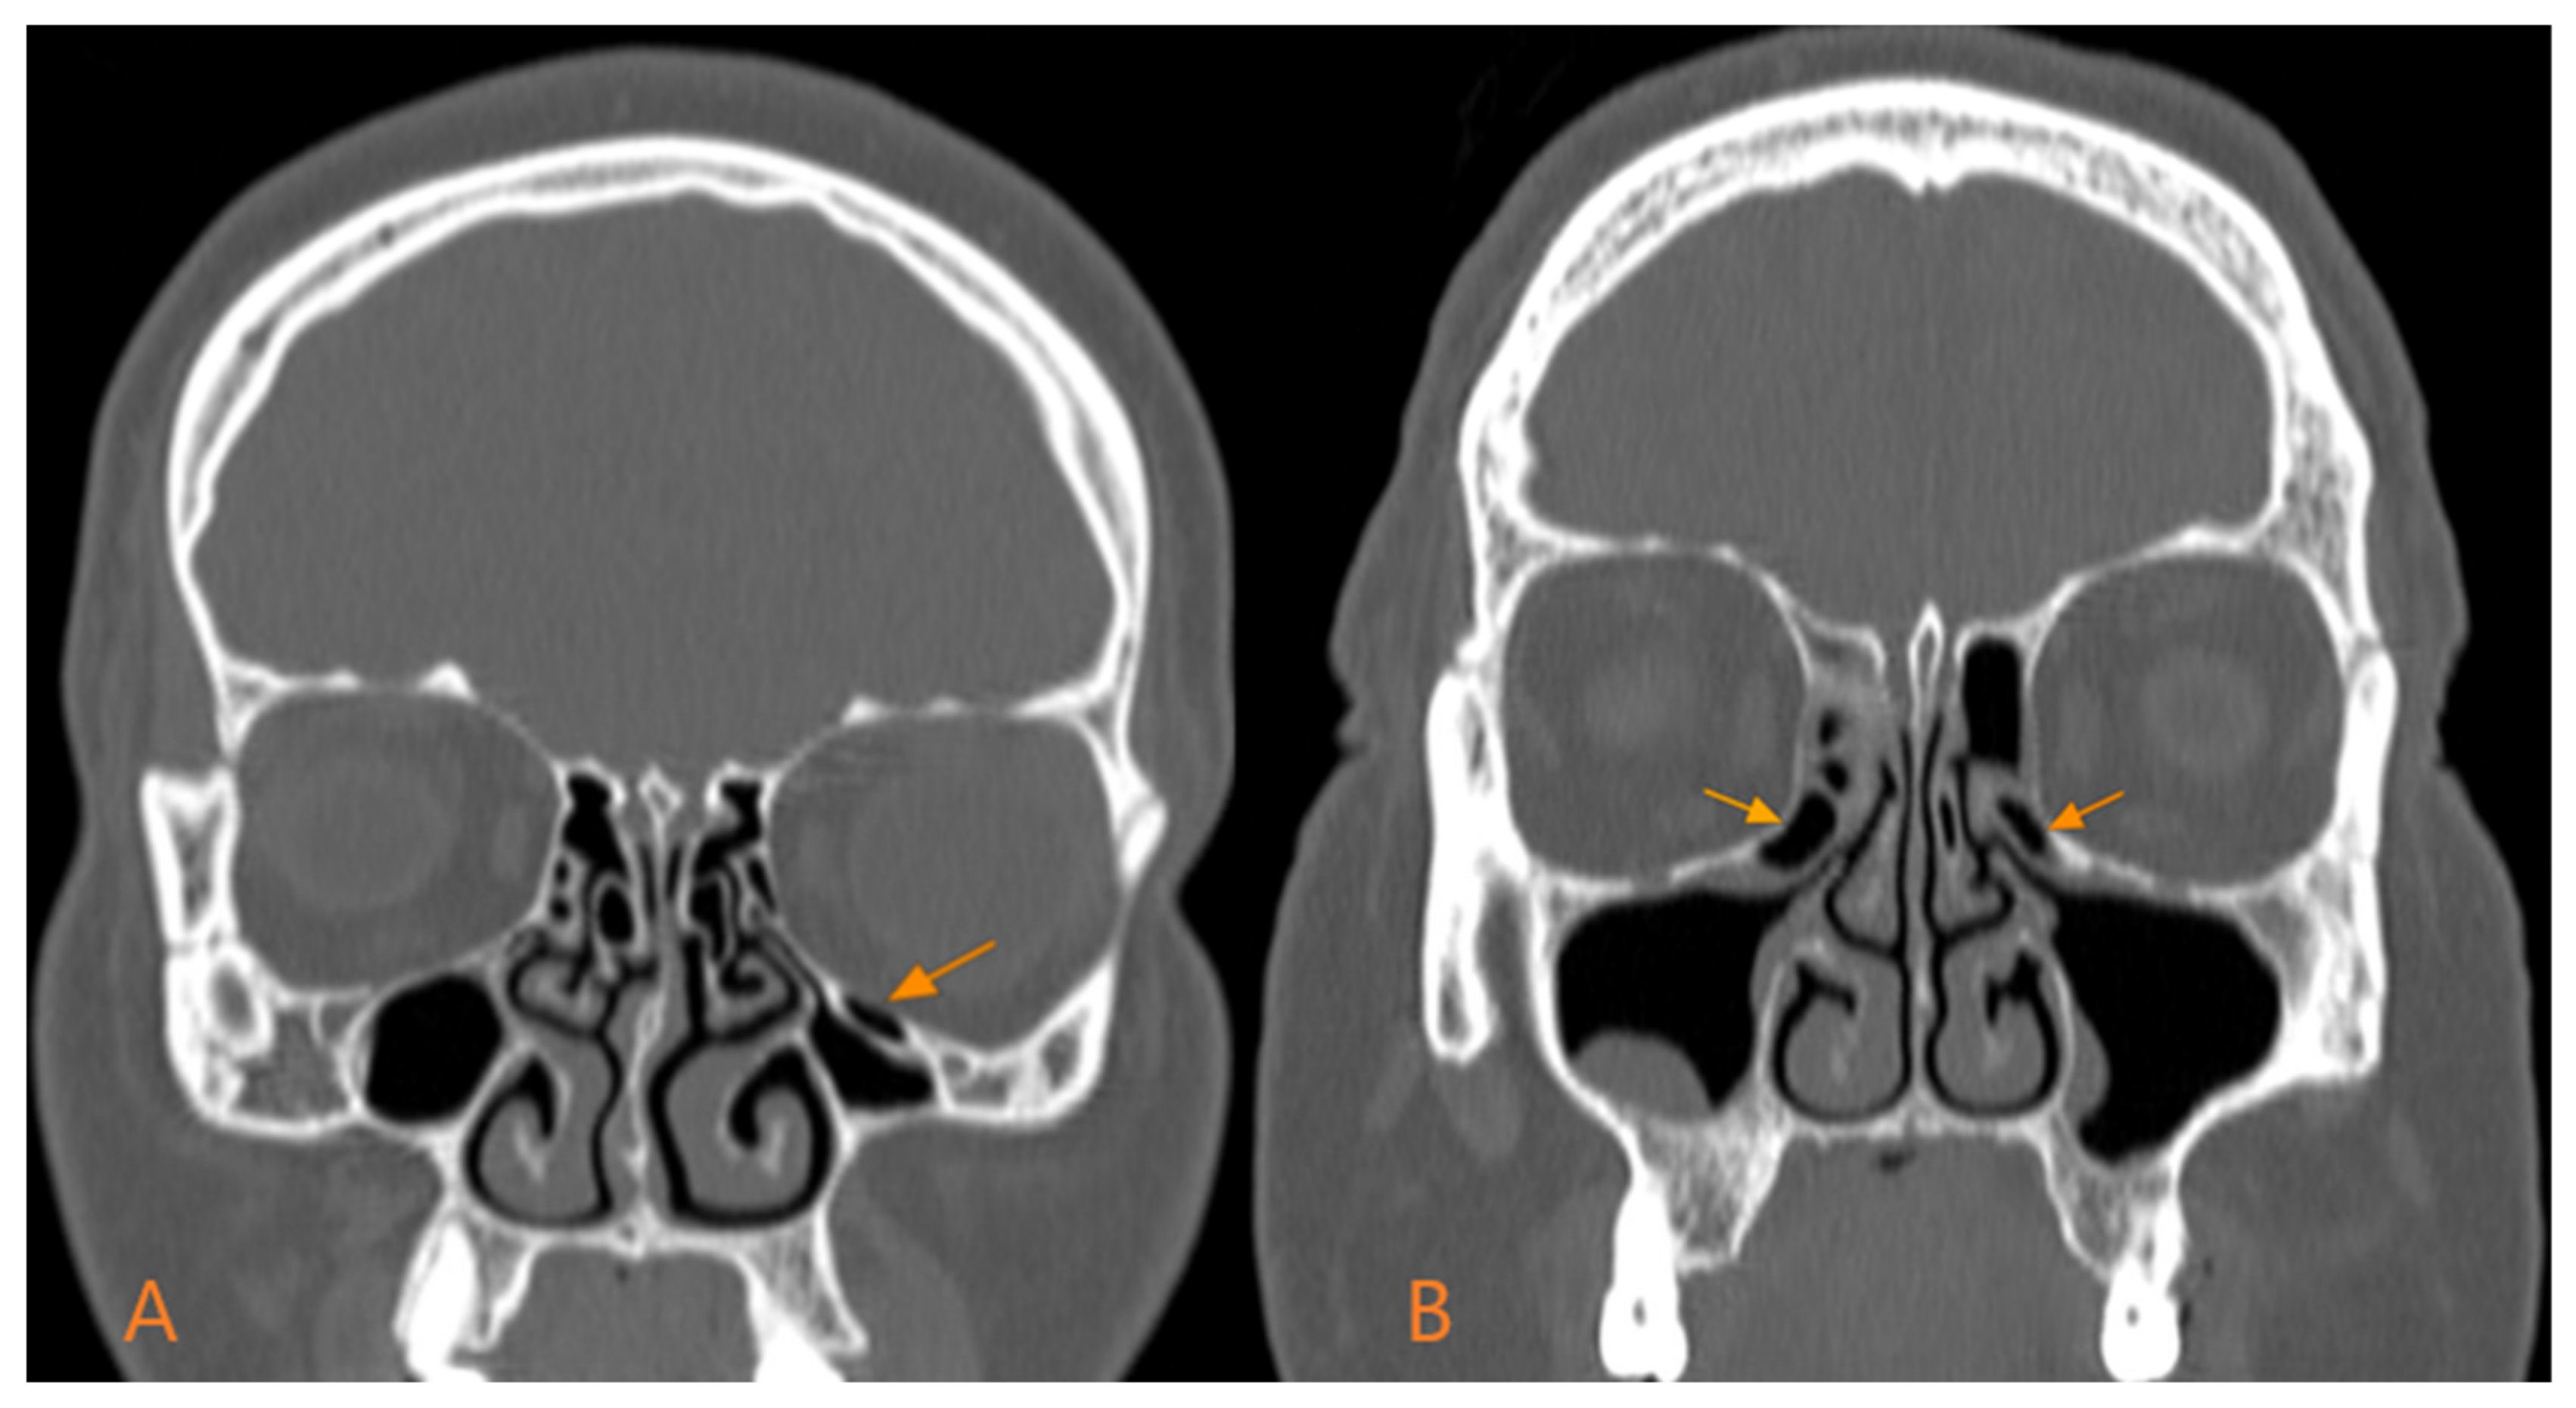

3.3. Location of Haller Cells According to Gender

We did not identify statistically significant differences regarding the unilateral or bilateral localisation depending on gender (p = 0.66) (Figure 1). In men, the bilateral type prevailed, with 65% (48 out of 74), while the unilateral type was in the minority, with 35% (26 out of 74). This pattern was also preserved in women, with 37 out of 54 (68.5%) presenting the bilateral type and only 17 out of 54 (31.5%) the unilateral type (Table 3).

Figure 1. Types of Haller cells according to location: (A)—unilateral; (B)—bilateral.